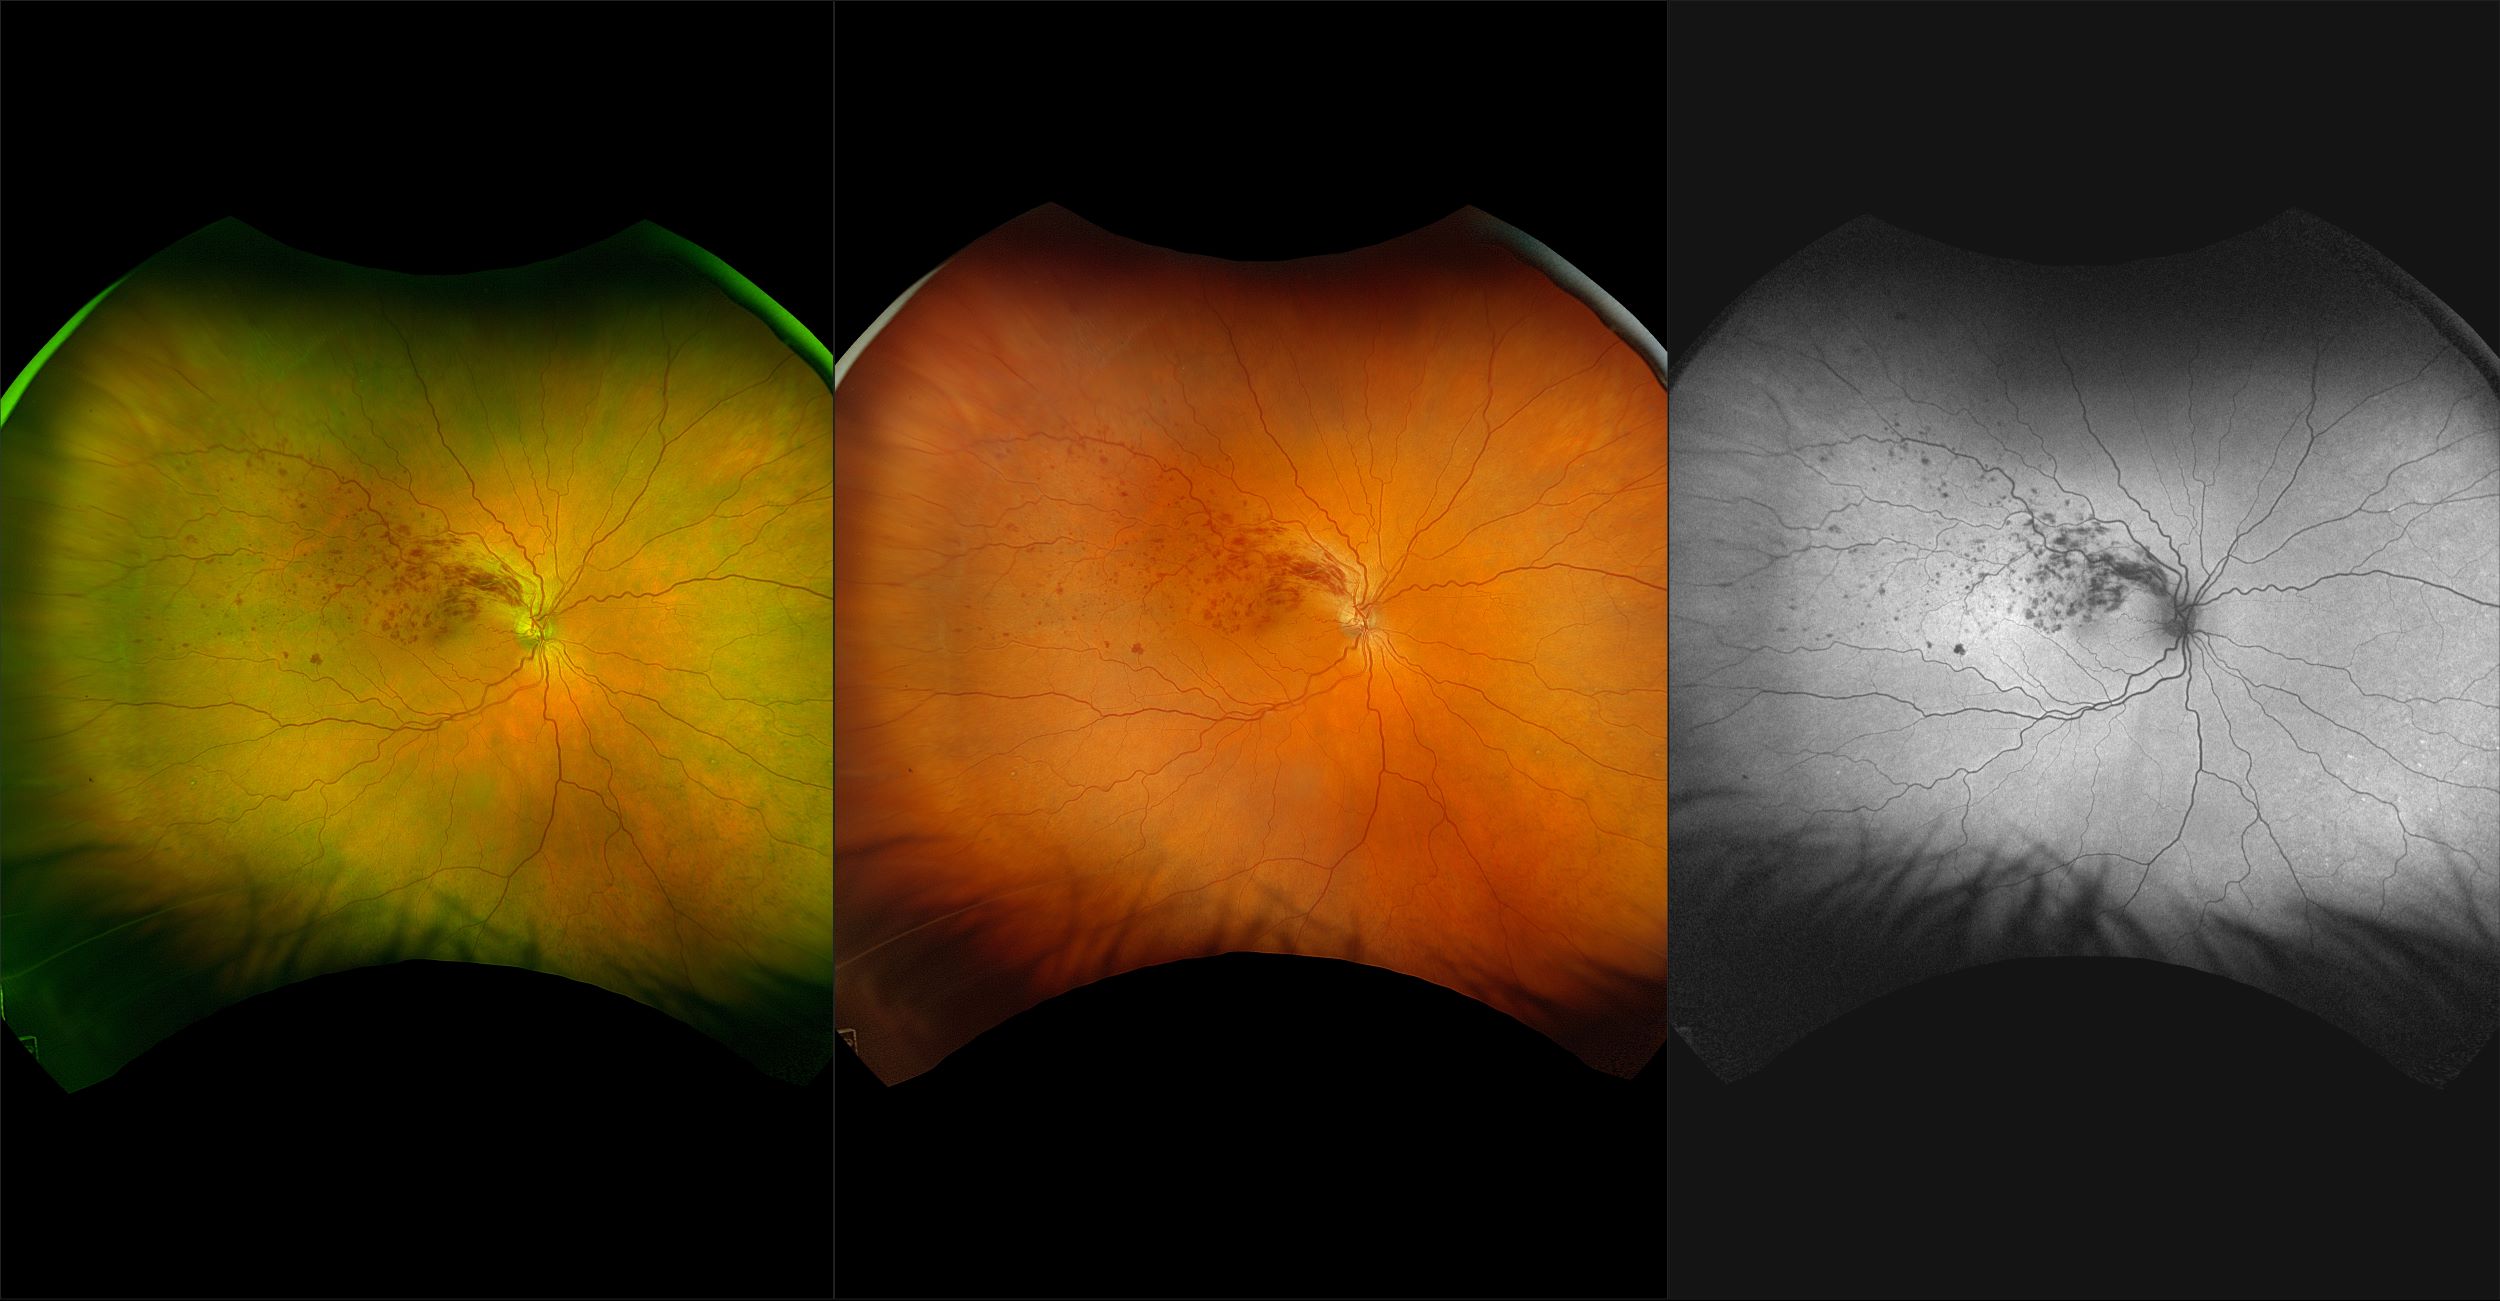

California - AMD, RG, AF

Age-related macular degeneration is found in two forms 1. Dry early form. 2. Wet (serous leakage or whole blood). Early dry form typically has drusen (usually around 63u) and RPE degeneration and only needs periodic follow-ups, intermediate dry form has large drusen (>125u) and RPE degeneration and proliferation which requires examinations every 3 to 6 months depending on the severity of the presentation.